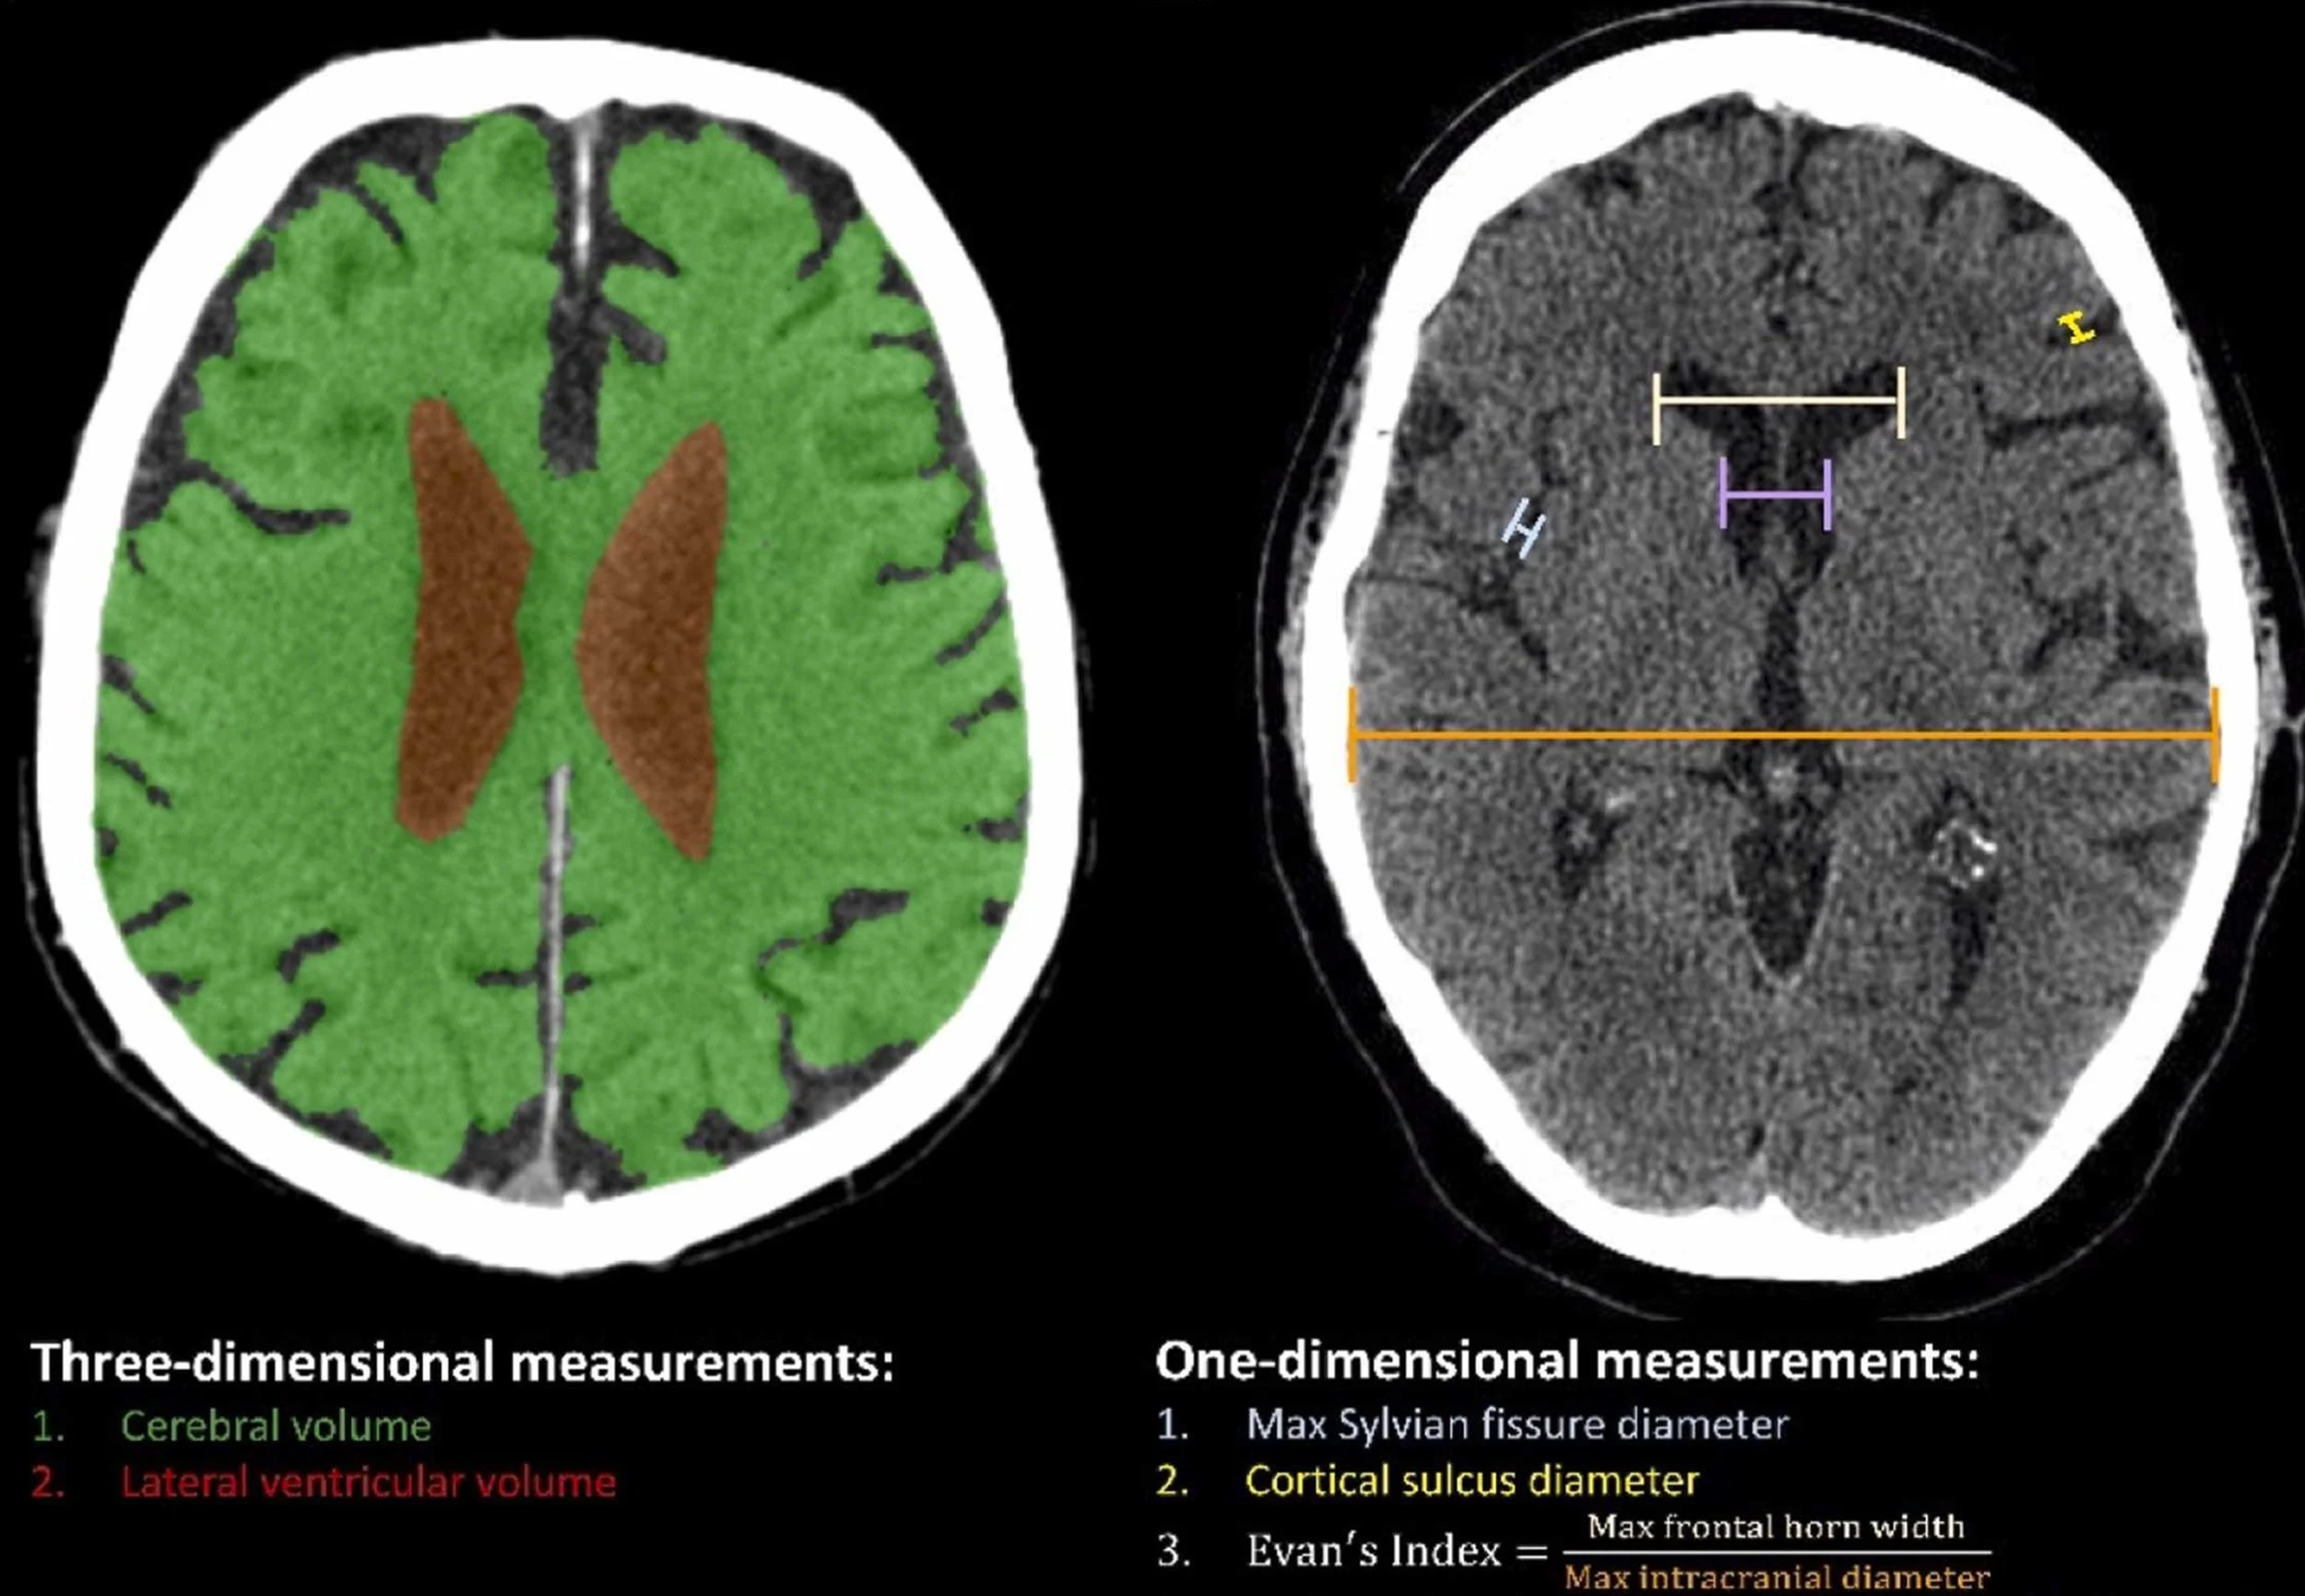

Serial neuroimaging and cognitive assessment characterizes the trajectory of cognition and brain atrophy after LVAD implantation.